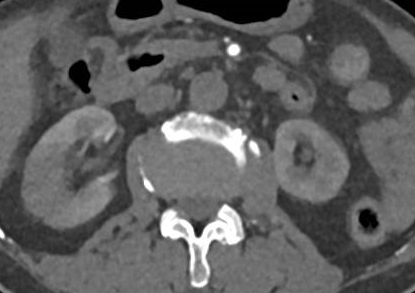

通过强化CT检查发现,患者腹主动脉肾动脉以远、左肾动脉及肠系膜下动脉开口处、双髂动脉及双侧下肢动脉血栓形成,右肾斑片状弱/无强化影,提示右肾梗死(图3-5)。

图3

图4

图5